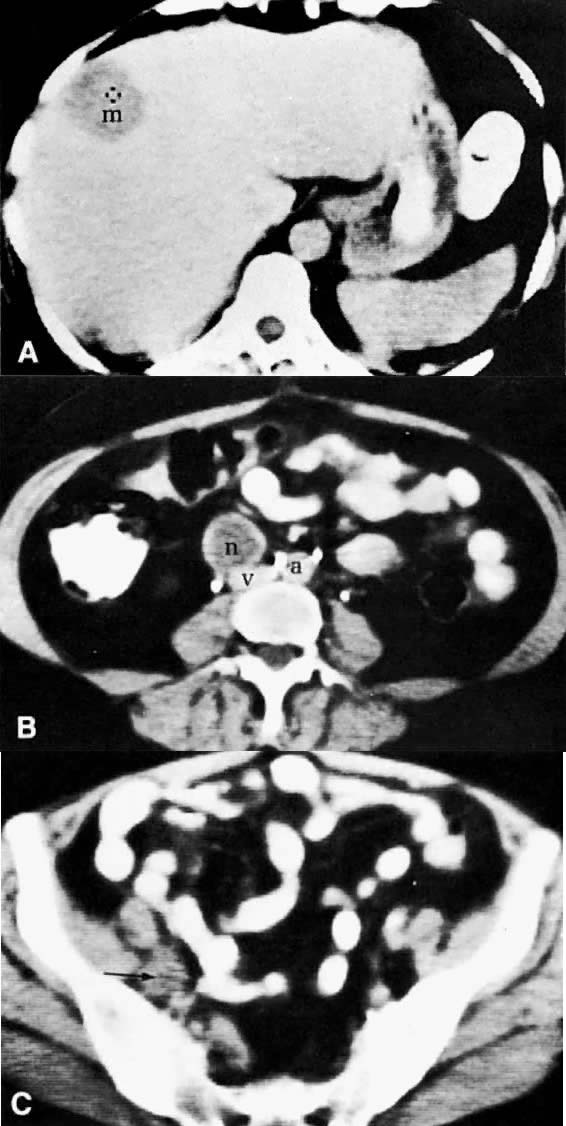

CT is a reasonably sensitive and specific modality for the detection of liver metastases.116 Most metastases are less dense than the normal liver parenchyma and are relatively well demarcated (Fig. 45A). Occasionally, however, the margins will merge imperceptibly with the liver parenchyma. Cystic metastases are seen with rapidly growing tumors, such as leiomyosarcoma. Peritoneal seeding on the liver capsule from ovarian neoplasms gives a characteristic scalloped appearance to the liver margin. Punctate or homogeneous calcifications can be seen in metastatic mucinous cystadenocarcinoma. New CT techniques, including spiral CT and CT angiography, are able to detect most hepatic metastases. The latter involves the introduction of contrast material directly into the superior mesenteric artery and allows improved contrast opacification of the liver and detection of very small metastatic deposits.

Fig. 45. Metastatic granulosa cell tumor. A. CT scan of the upper abdomen shows a low-density, well-marginated mass ( m) in the right lobe of the liver. B. Lower abdominal CT scan shows a necrotic paracaval mass ( n) consistent with lymphadenopathy. C. CT scan of the pelvis shows an enlarged right external iliac lymph node ( arrow) measuring 1.5 cm in diameter with some necrotic changes seen in its center. ( a, aorta; v, inferior vena cava.)

Both CT and MRI have replaced lymphography in detecting tumor spread to the lymphatic system. CT has a reported accuracy of 83% and a specificity of 86% in detecting metastases to the para-aortic lymph nodes.122 Although CT is useful in detecting small lymph nodes within the pelvis, it is slightly less accurate (70% to 80%) in detecting metastases to pelvic lymph nodes compared to para-aortic lymph nodes, because of the sparsity of fat around the former.25

The diagnosis of lymph node metastases by CT depends predominantly on the increase in their size, but occasionally there is also a change in density (see Fig. 45B and Fig. 45C). Normal lymph nodes measure less than 1 cm in diameter. An isolated para-aortic or iliac lymph node measuring 1 to 1.5 cm should be considered suspicious (see Fig. 45C), and a clustering of small lymph nodes should be considered abnormal (see Fig. 38C). Lymph nodes larger than 1.5 cm in diameter also should be considered abnormal (see Fig. 45B).123 Metastatic lymphadenopathy is occasionally visualized as a conglomerate group of contiguous enlarged lymph nodes similar in size to the aorta or inferior vena cava, or as a large, homogeneous mass (see Fig. 48A).124 A false-negative diagnosis by CT is caused by the technique's inability to diagnose metastases in normal-sized lymph nodes. Because metastases from cervical carcinoma often replace part of a lymph node without enlarging it, the reported false-negative rate has been as high as 40%.25 A false-positive diagnosis results from the inability of CT to differentiate enlarged nodes caused by hyperplasia from those caused by metastases. CT-guided percutaneous fine-needle aspiration biopsy of the enlarged lymph nodes may be required (Fig. 49). Extension of tumor into lymph node groups not opacified by lymphography (e.g., mesenteric lymph nodes) can also be detected by CT, and biopsy specimens of these nodes can be taken during CT scanning.